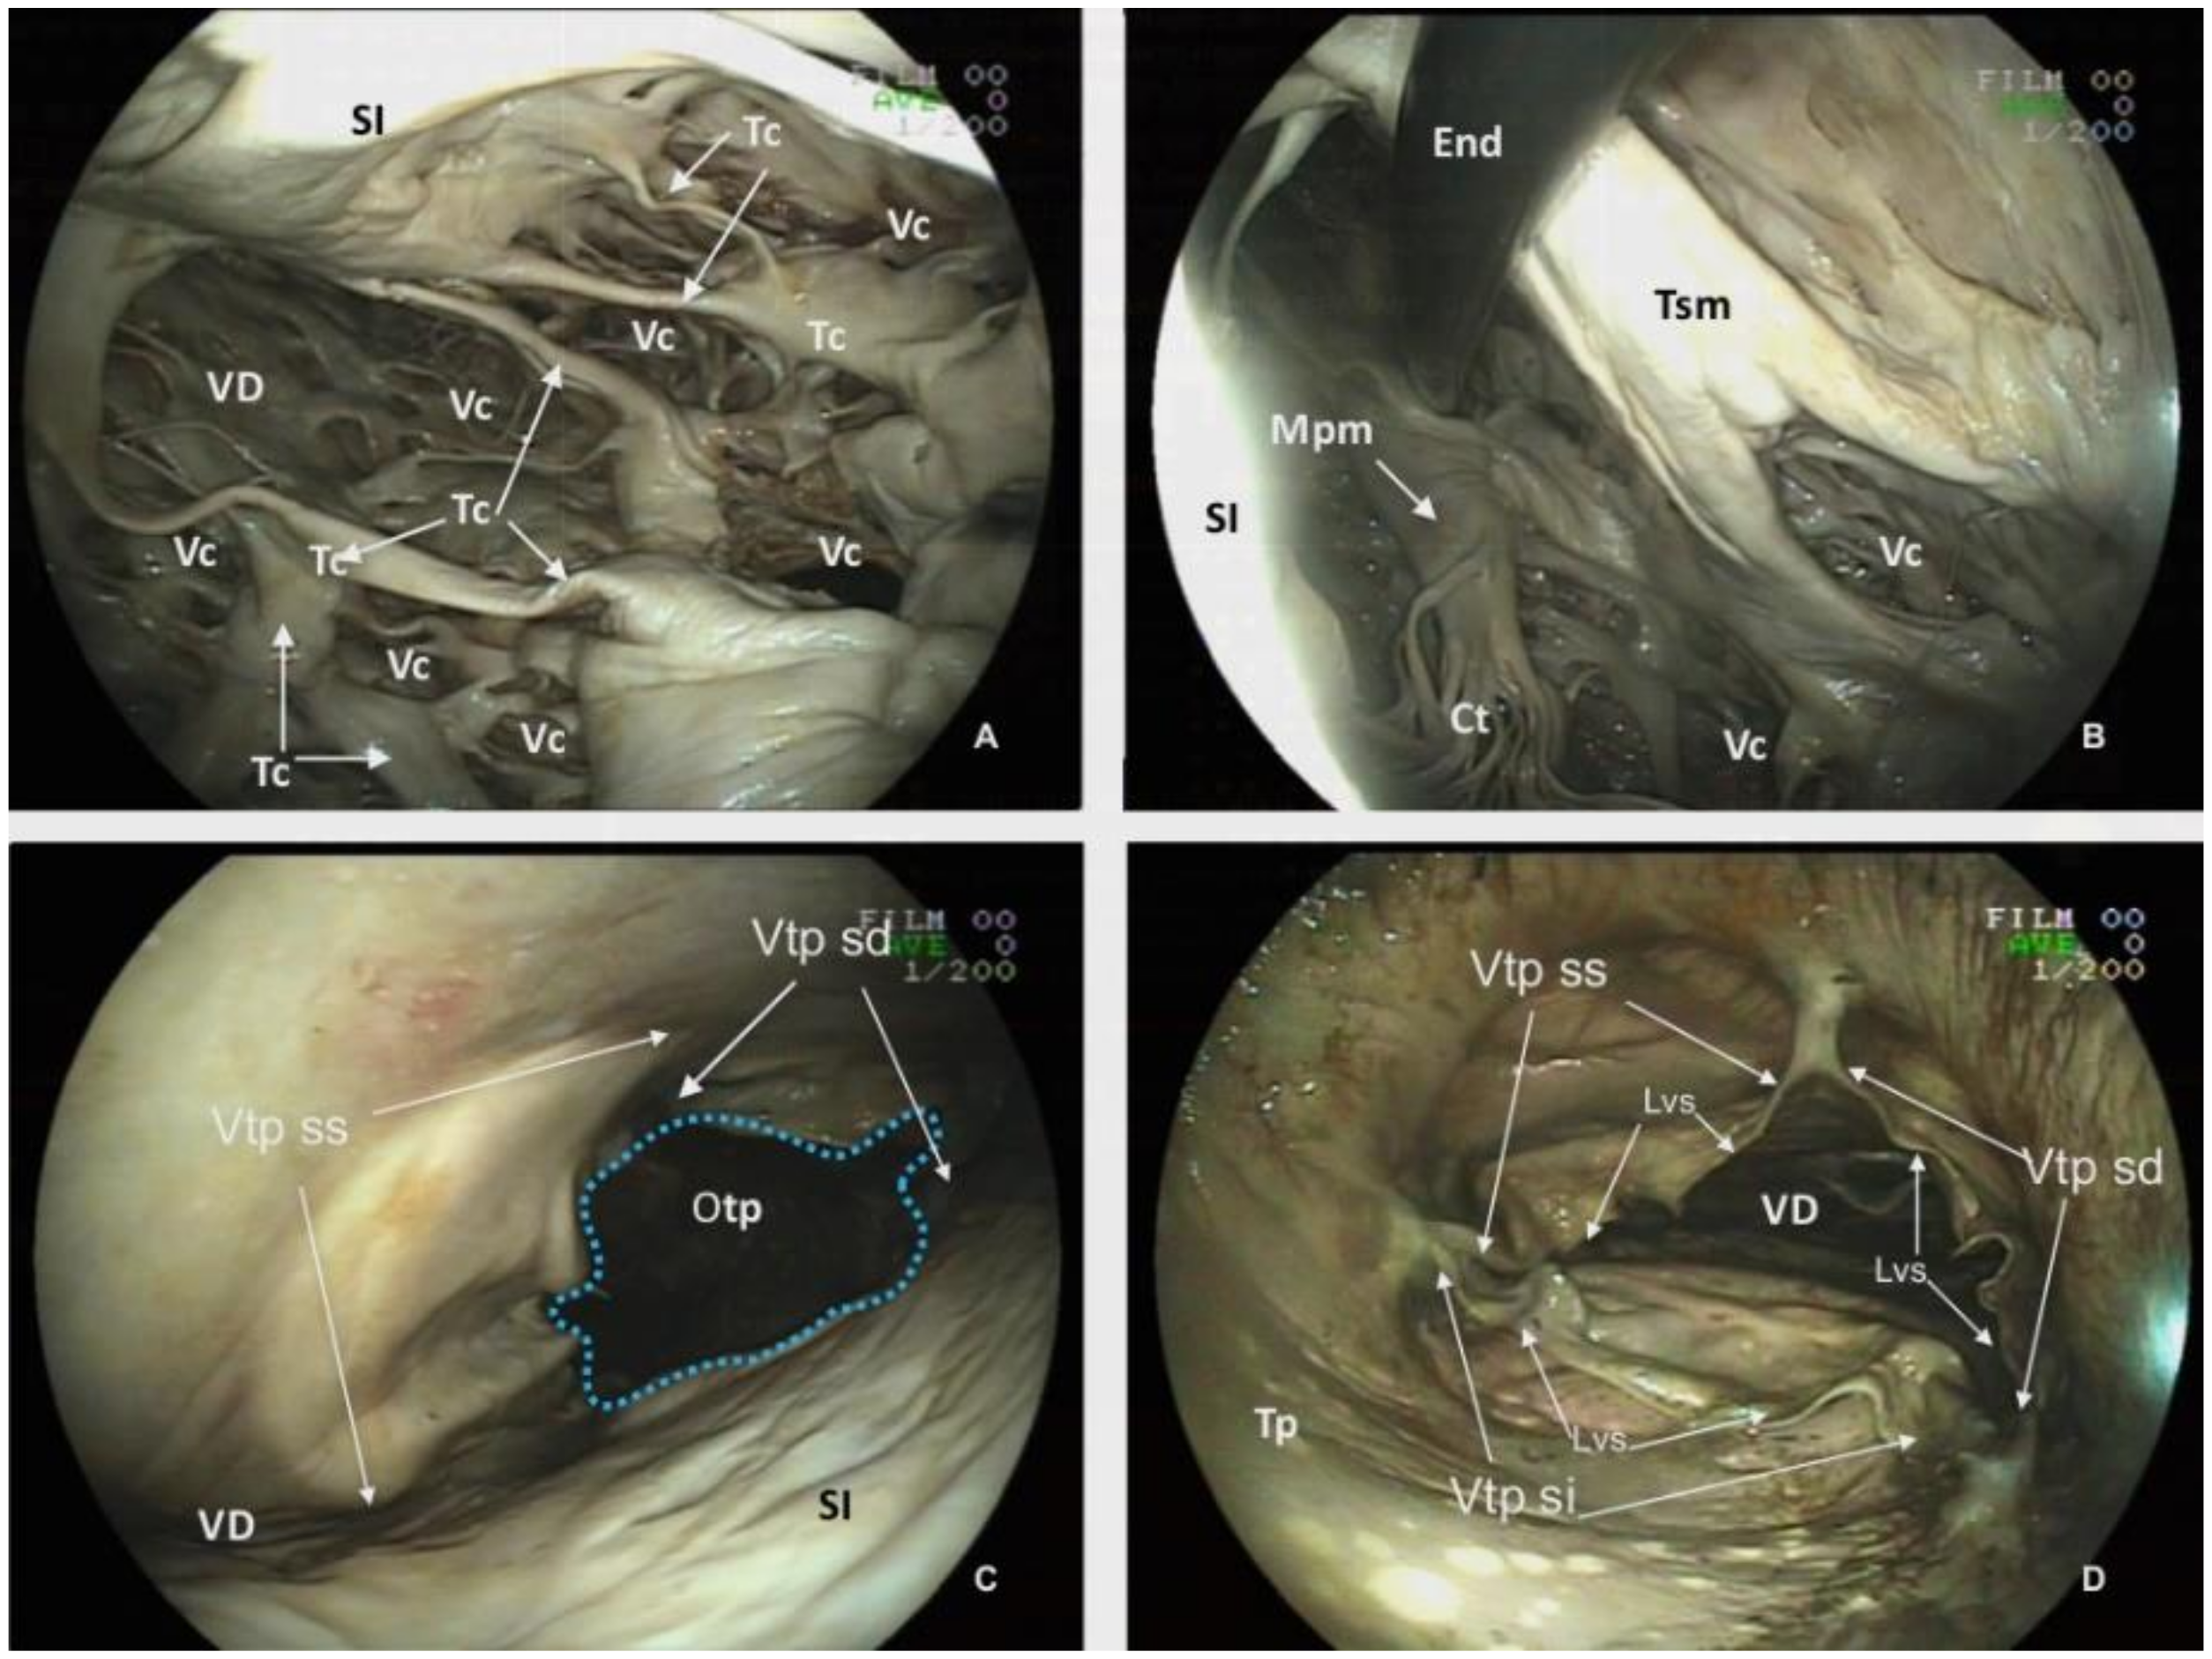

The CT and endoscopic images revealed intramyocardial vascular caverns within both the interventricular septum and the parietal walls of the ventricles (Figure 6, Figure 8A and Figure 9A). The estimated proportion of myocardial area occupied by these caverns in the interventricular septum is: 13.78% (I), 23.5% (II) and 7.49% (III); in the wall of the right ventricle: 69% (II) and 65.09%, (III); and for the wall of the left ventricle: 11.61%(I), 18.4% (II) and 17.89% (III).

Another unique feature of the killer whale heart is the numerous Trabeculae carneae found within the ventricles. Those trabeculae involve myocardium and endocardium and create a conspicuous and complex mesh of projections protruding into the lumina (Figure 8A).

Another relevant structure of the Ventriculus dexter is the Trabecula septomarginalis, which courses from Septum interventriculare to the parietal wall. This distinctive trabecula is not a unique fascicle, but consists of a principal fascicle with a length of 20.31 cm and a thickness of 4.70 cm with associated projections (Figure 8B).

The Ventriculum dexter communicates with the Truncus pulmonaris by the Ostium trunci pulmonalis (Figure 8C,D), which has an internal diameter of 8.64 cm. The lumen of this orifice is regulated by the Valva trunci pulmonalis which has three cusps, the Valva semilunaris intermedia (7.83 cm width), the Valva semilunaris dextra (4.93 cm length) and the Valva semilunaris sinistra (5.46 cm length). Despite a careful inspection with the endoscope, a Noduli valvularum semilunarium is not identified; however, Lunulae valvularum semilunarium are visible along the valve margins (Figure 8D).

Figure 8. Endoscopic view of the Ventriculus dexter (VD) of the plastinated killer whale heart. (A) and (B): Lumen of the Ventriculus dexter. (C): Ventral view of the pulmonary truck valve from the left Ventriculus sinister. (D): Dorsal view of the Valva trunci pulmonalis, from the lumen of the Truncus pulmonalis (Tp). Vascular caverns (Vc), Trabeculae carneae (Tc) Chordae tendineae (Ct), Trabecula septomarginalis (Tsm), Musculus papillaris magnus (Mpm), Septum interventriculare (Si), Ostium trunci pulmonalis (Otp), Valva trunci pulmonalis (Vtp): Valva semilunaris intermedia (Vtp si), Valva semilunaris dextra (Vtp sd), Valva semilunaris sinistra (Vtp ss), Endoscope (End), Lunulae valvularum semilunarium (Lvs).